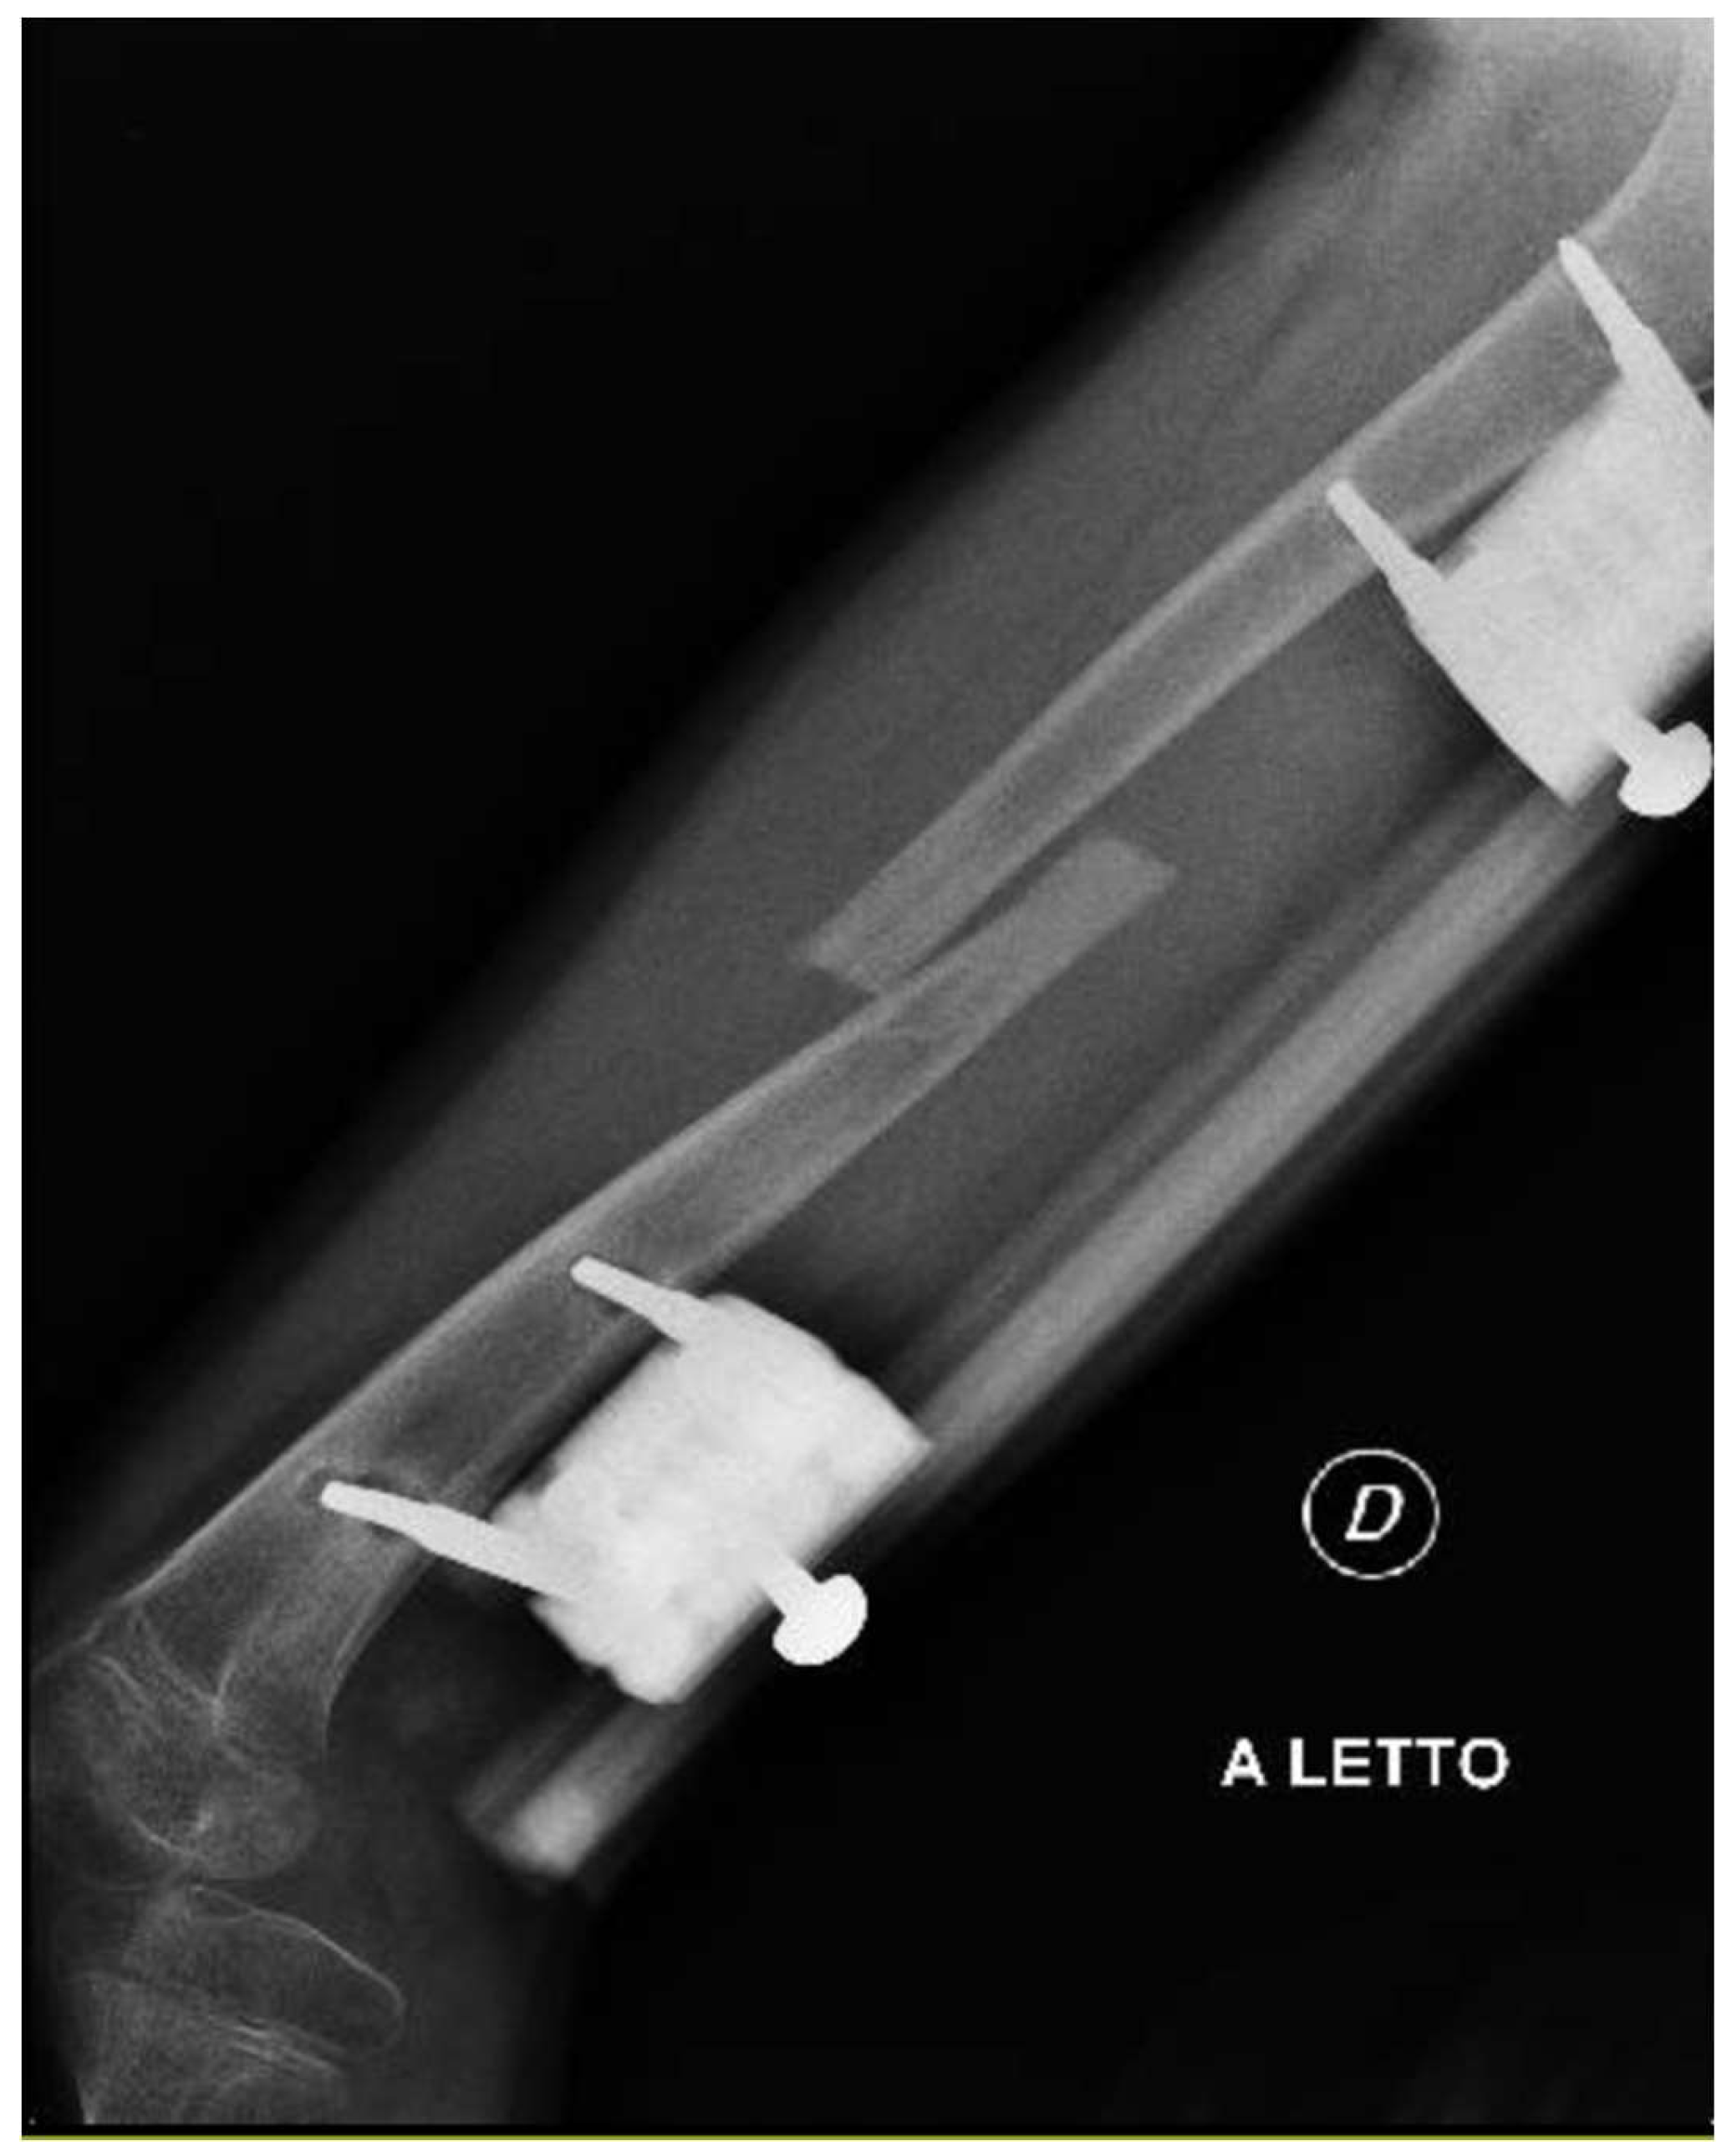

The patient was instructed to start physical therapy for hip and knee range of motion immediately after surgery, while progressive weight-bearing was commenced on the last day of lengthening. At 12 weeks the lengthening goal, 60 mm, was achieved. At 5-months follow up, lower-limb weight-bearing plain radiographs demonstrated that the right femur was within 5 mm of length of the left femur and bone regeneration was visible in the osteotomy gap, however, the study was limited by the inability to fully extend the right knee (Figure 2). Lateral projection radiographs of the right knee showed posterior subluxation of the tibia with respect to the femoral condyles (Figure 3). No action was taken at the time.

The patient presented to our attention at about 6 months post-surgery complaining of acute pain and deformity at the middle third of the thigh. Radiographs showed fracture of the femoral regenerate (Figure 4). The patient underwent immediate external fixator removal, reduction of the knee dislocation and finally Elastic Stable Intramedullary Nailing (ESIN) of the femoral fracture prior attempt to ream the femoral canal losing 20 of the 60 mm lengthened (Figure 5). Ten months after the procedure, the patient underwent nail removal for complete fracture consolidation.